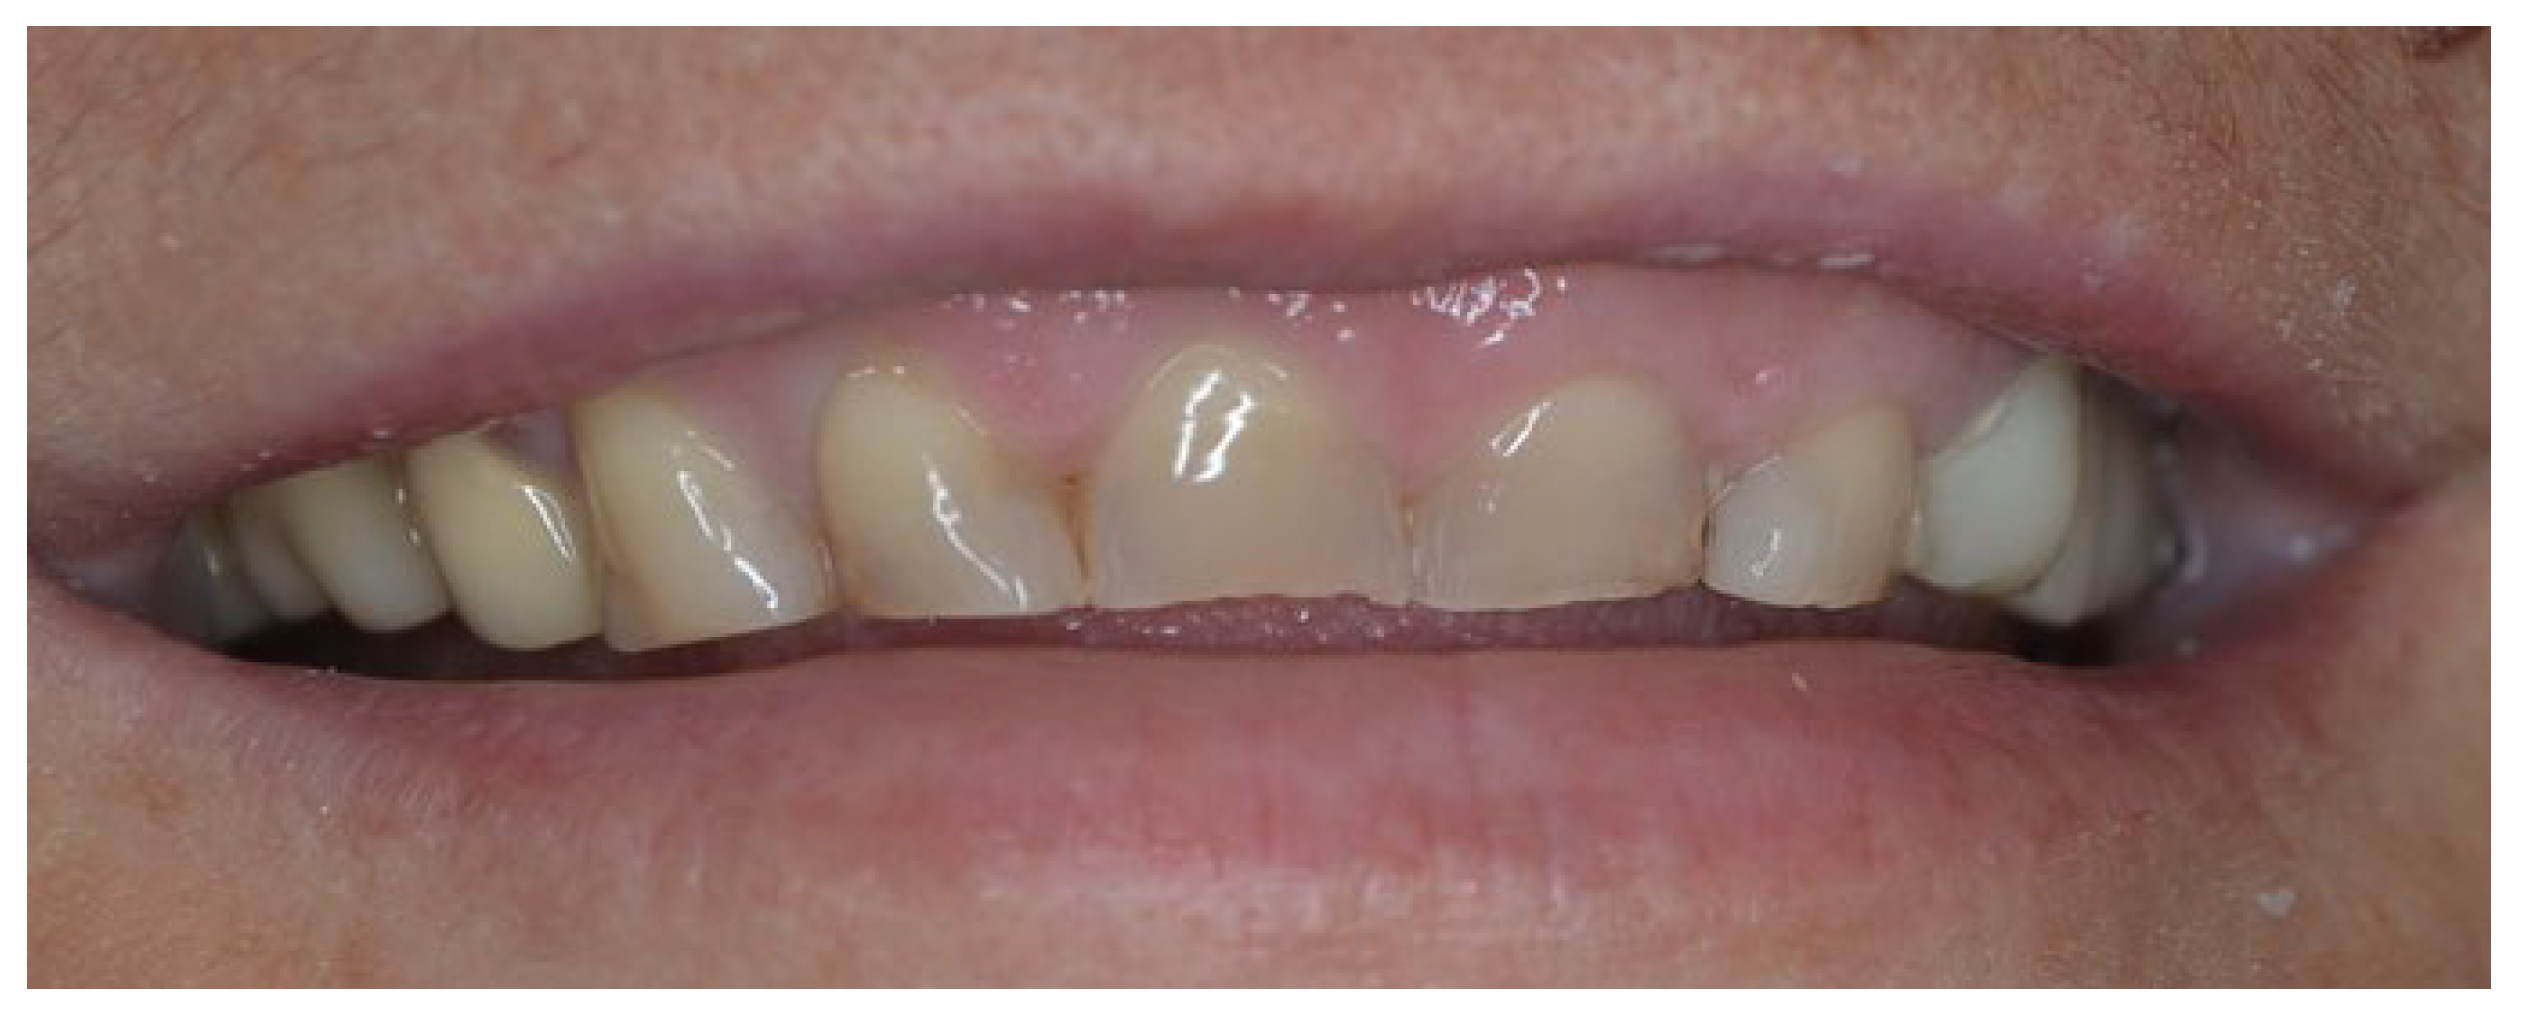

4.1. Case 1

4.2. Case 2